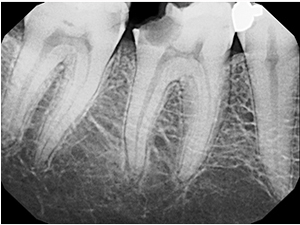

Images of case of RCT

Case : Single Sitting Protaper Molar Rct

Before Treatment